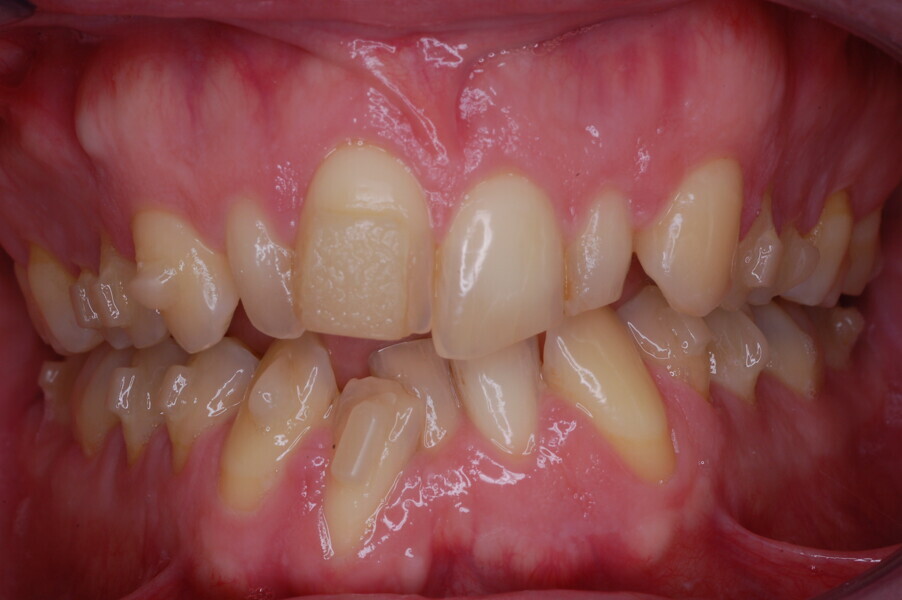

A healthy 39-year-old man presented to our orthodontic office with the chief complaint of an unattractive dental appearance and fear of the orthognathic surgery proposed by another orthodontist. Clinically, the patient’s profile was straight, and the frontal view did not show any facial asymmetry. The functional examination did not reveal any mandibular deviation or reduced movements. The patient had no joint pain, and no joint noise was observed.

Figs. 1–8: Pretreatment facial and intra-oral photographs.

From the periodontal point of view, the patient showed a good attitude to oral hygiene, but crowding of the mandibular incisors made cleaning difficult in that area, causing plaque accumulation and localised gingival inflammation. The panoramic radiograph revealed the presence of the mandibular third molars and confirmed the absence of the mandibular right central incisor (Fig. 10).

The cephalometric analysis showed a skeletal Class II malocclusion (convexity of Point A: 4.9 mm), a slightly retruded chin position (facial depth: 78.1°) and a skeletal open bite tendency (lower facial height: 53.19°; facial axis: 80.58°; Fig. 9). The mandibular incisors were lingually tipped (Li–APog: 9.3°) and retruded (Li–APog: 1.55 mm), and there was an increased inter-incisal angle of 142.9°.